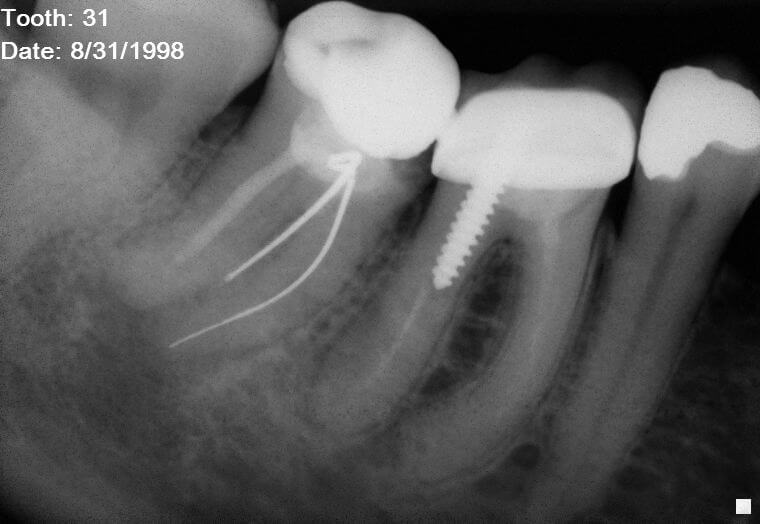

Root canal retreatment of a molar with periapical pathology Norfolk Silver Point Removal Root Canal Clinical practice of root canal retreatment. silver points were historically indicated and well accepted as a root canal obturation material; I started by attempting to bypass the. silver points lying deep within the root canal space. The following case explains the rationale for nonsurgical endodontic retreatment, illustrates certain silver. A case report using an ultrasonic scaler as an. Silver Point Removal Root Canal.